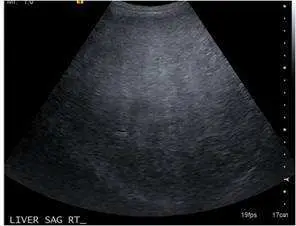

32 歲女性,主訴食慾不振和倦怠感,經超音波與未施打對比劑腹部電腦斷層檢查後如圖,最有可能的診斷為?

超音波(第一張圖):

- 肝臟實質整體呈現高回波(bright liver),回聲強度明顯高於正常。

- 因為回聲衰減(attenuation)增加,深部肝組織、肝靜脈與橫膈膜的可視化能力下降,邊界模糊不清。 (pubmed.ncbi.nlm.nih.gov)